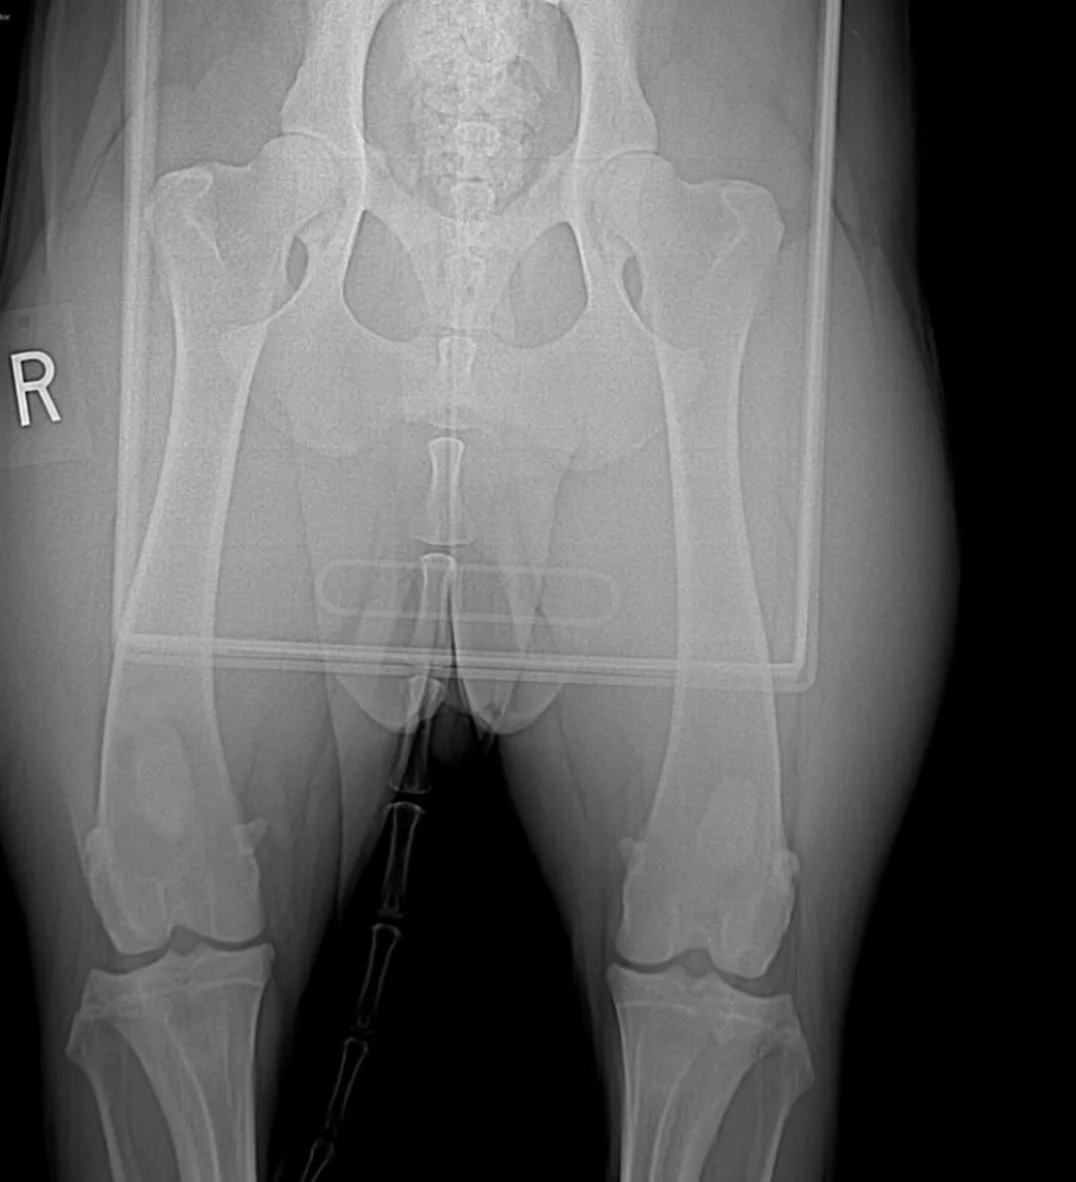

Kurenai’s hip xray at 35 months old. OFA Hips EXCELLENT and OFA Elbows NORMAL.

• OFA Hips: EXCELLENT

• OFA Elbows: NORMAL